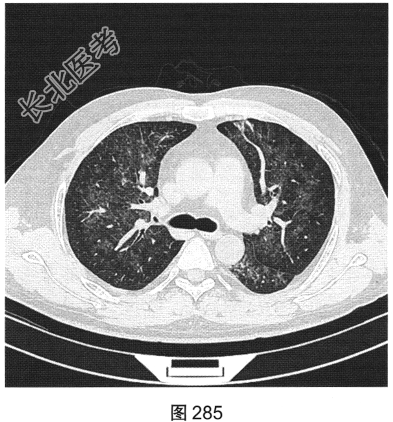

- [材料题] 患者男性,33岁,因“双下肢散在皮下出血点伴尿检异常3个月余,咳嗽、胸闷伴发热一周”就诊。患者脂肪肝、胆囊炎,服用莲葡双清片;随后几日内食用淡水鱼、鱿鱼、饮啤酒;5天后出现双下肢散在皮下出血点,未重视;10天后出现腹痛,在当地医院检查尿中有蛋白、定量不详,血常规检查正常,肾功能正常,应用醋酸泼尼松效果欠佳,行肾活检术,病理诊断:紫癜性肾炎,继发IgA肾病。患者每天静脉滴注甲泼尼龙0.5g,共3天,后改为口服甲泼尼龙28mg/d,共35天。一周前着凉后出现咳嗽、胸闷伴发热,体温达39.1℃,于当地医院抗炎治疗效果欠佳,遂来本院。实验室检查:血白细胞计数6.92×109/L,中性粒细胞0.845,CRP为2.7mg/dl。患者PP65阳性。胸部CT检查如图284~图287所示。

- 多项选择题1.患者的主要影像特征是( )

A、双下肺为著

B、伴细网格影

C、血管支气管束增厚

D、小叶中央结节

E、以磨玻璃密度为主

F、双肺弥漫分布

- 多项选择题2.根据患者病史和影像特征,您的诊断是( )

A、肺结核

B、巨细胞病毒感染

C、急性肺泡损害

D、外源性过敏性肺泡炎

E、肺水肿

F、肺孢子菌感染